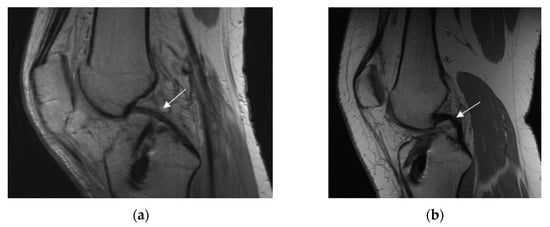

3.2.2. Posterior Cruciate Ligament (PCL) Buckling (Subluxation)